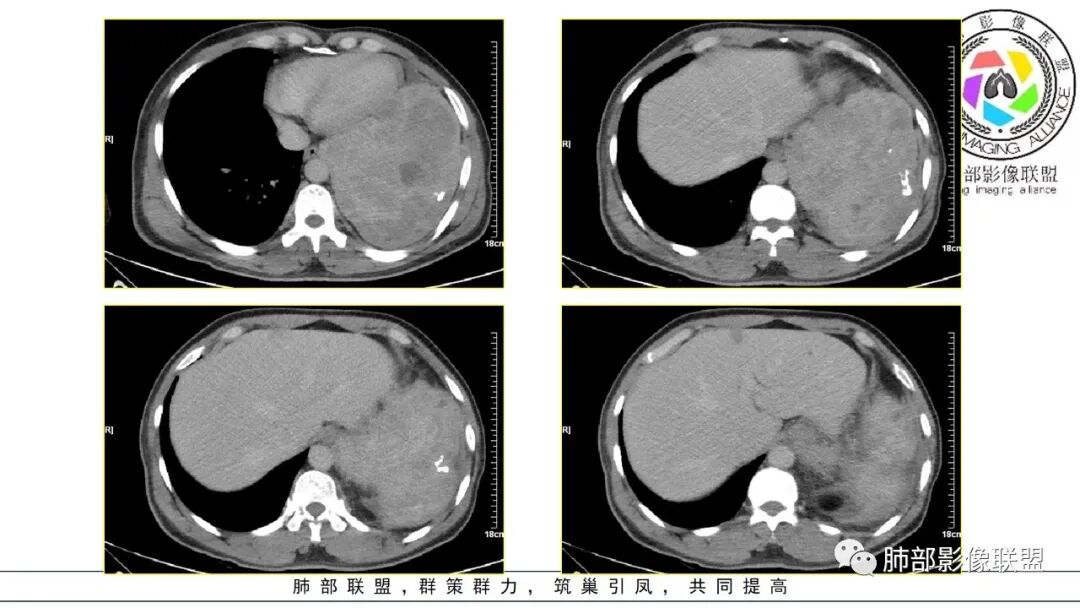

男,50岁,双下肢水肿10余天,发热3天。NSE、细胞角蛋白19片段增高。胸部CT:肺气肿背景,左下叶巨大肿块,边缘膨隆明显,与周围界限清楚,累及左肺门、左上叶,上叶支气管受压狭窄,下叶支气管截断,不均匀强化,湖泊样坏死,肿块边缘粗大点状钙化,肿块内血管影迂曲、模糊,蛇纹?考虑恶性,鳞癌?肉瘤样Ca?鉴别SFT。

2.左肺巨大块影,上部边界较清楚,占据胸腔大部,对于左肺,“占据”及“推移”兼而有之,左肺上叶支气管推移狭窄,下叶支气管截断。下肺动脉穿行!

3.病灶密度不均,轻度强化,坏死或液化范围甚大,边界可分辨,部分“壁”可见钙化。

4.病灶紧贴胸壁,胸壁未见栽赃侵入。

5.纵隔左移,左肺门变形。左肺门及纵隔未见明显增大淋巴结。